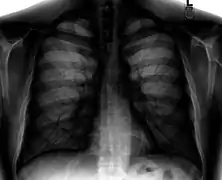

![]() A normal posteroanterior (PA) chest radiograph of someone without any signs of injury. Dx and Sin stand for "right" and "left" respectively. | |